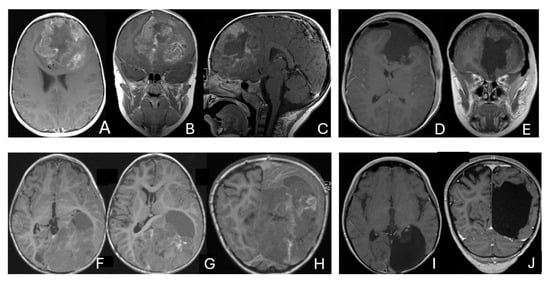

Circulating Tumor Cells in Glioblastoma

Robert H. Eibl and Markus Schneemann

Glioblastoma multiforme (GBM) remains a devastating brain tumor with poor prognosis, traditionally viewed as non-metastatic. The recent detection of circulating tumor cells (CTCs) in glioblastoma challenges this long-held view and opens new opportunities for liquid biopsy in neuro-oncology. This review summarizes current understanding of glioblastoma CTCs, emphasizing their unique properties, detection technologies, and differences compared to CTCs in extracranial cancers. Key challenges include their rarity, the absence of epithelial markers, and the presence of the blood–brain barrier. Despite the need for specialized enrichment approaches, CTC analysis in glioblastoma can offer helpful information regarding tumor heterogeneity, treatment response, and minimal residual disease. We discuss emerging clinical studies leveraging CTCs for early relapse detection and therapy monitoring. Integrating CTC phenotyping with molecular and functional characterization may enhance future personalized treatment strategies in glioblastoma. Refined CTC methodologies combined with other liquid biopsy modalities may transform glioblastoma management, improving patient outcomes through less invasive, dynamic tumor surveillance.

Full article